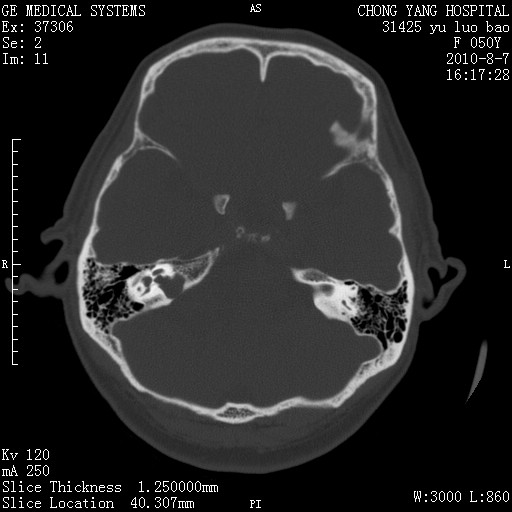

标题: CT28285:听力下降一年,头昏。

右侧桥小脑角区占位--听神经瘤,建议增强或mri检查。

右侧桥小脑角去等密度占位,右侧内听道扩大、骨质吸收,考虑:右侧听神经瘤,建议增强检查。

右侧内听道扩大、骨质吸收,中脑受压左移,考虑:右侧听神经瘤,建议增强检查。支持!

骨窗示右侧内听道扩大,考虑右侧听神经瘤。

右侧桥小脑角区等密度占位,内耳道扩大,听神经瘤